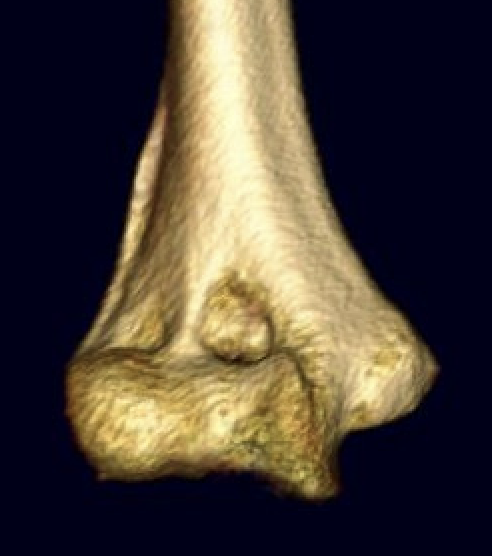

Type C: Complete articular fractures

CT scan